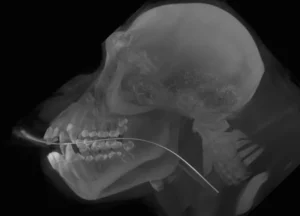

With this CT imaging system the entire head can be imaged in a single 18 second scan, allowing evaluation of teeth, jaw bones, maxillofacial anatomy, sinus and nasal cavities. CT images are composed of slices which allows millimeter by millimeter detailed assessment. In addition, a computer-generated three dimensional image may be produced. These images are superior to regular x-rays for evaluation of maxillofacial fractures, temporomandibular joint dislocations, and oral cancer.

Sample Images